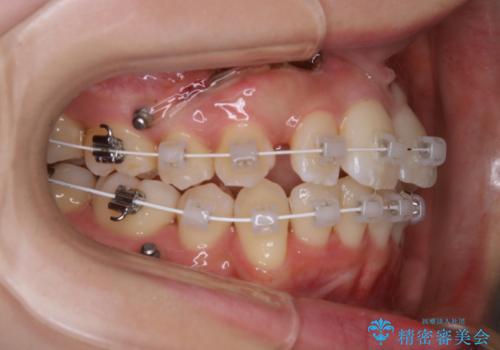

がたつきが強いガチャ歯。埋伏歯抜歯+矯正。すごいところに犬歯が埋まっていたのを抜いてワイヤー矯正治療

- 矯正装置

- ワイヤー矯正 審美装置

- 歯のがたつきを主訴に来院されました。

がたつきの強さから4本抜歯の必要性がありましたが、右上の歯は犬歯が一本埋まっており、乳歯がある状態でした。

右上については先に乳歯を抜歯して、犬歯が使えるようであれば第一小臼歯を抜歯することとして治療を開始しました。

当初、犬歯が動くようであれば代わりに小臼歯を抜歯する予定でしたが、

開窓して器具で力をかけても動く様子がなかったため抜歯とし、小臼歯を犬歯に見立てて治療を完了しました。

結果的に見た目の違和感もなく、期間の短縮にもつながりました。